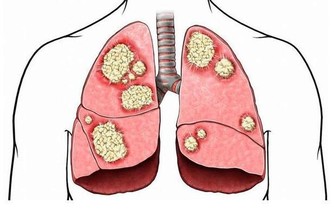

胸悶、胸痛是血栓來臨最常見的症狀之一。因為血栓初期,血管中非常容易出現凝結而成的血栓,如果其掉落並隨血液流入肺部,可能引發胸悶胸痛症狀。

一旦形成肺栓塞,隨著呼吸疼痛會逐漸加重,且一般是刺痛或銳痛。因此,如果身體出現胸悶胸痛一定要特別警惕,尤其是老年人。